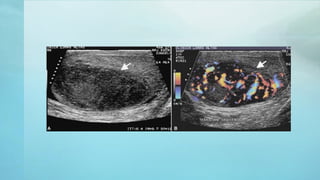

DIAGNÓSTICO CON IMÁGENES.

ECOGRAFÍA

• Confirma la presencia de masa

testicular y explora el testículo

contralateral.

• Tiene sensibilidad del 100% y

hace la diferencia entre masa

intra o extratesticular.

• Se debe realizar en jóvenes sin

masa testicular palpable pero

con masas viscerales o

retroperitoneales o cuando hay

elevaciones de AFP y GCH.